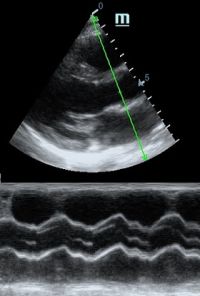

Но как же провести стандартные измерения в М-режиме, если мы его не использовали? На помощь приходит функция Free Xros M – анатомический М-режим. Имея записанную в память прибора видео петлю, мы можем провести линию М-режима в любом месте, при этом корректируя изначально не оптимальный угол.

Оценка кооптации нижней полой вены ещё никогда не была такой простой и точной, никаких лишних деталей, просто устанавливаем клипер по анэхогенному участку.